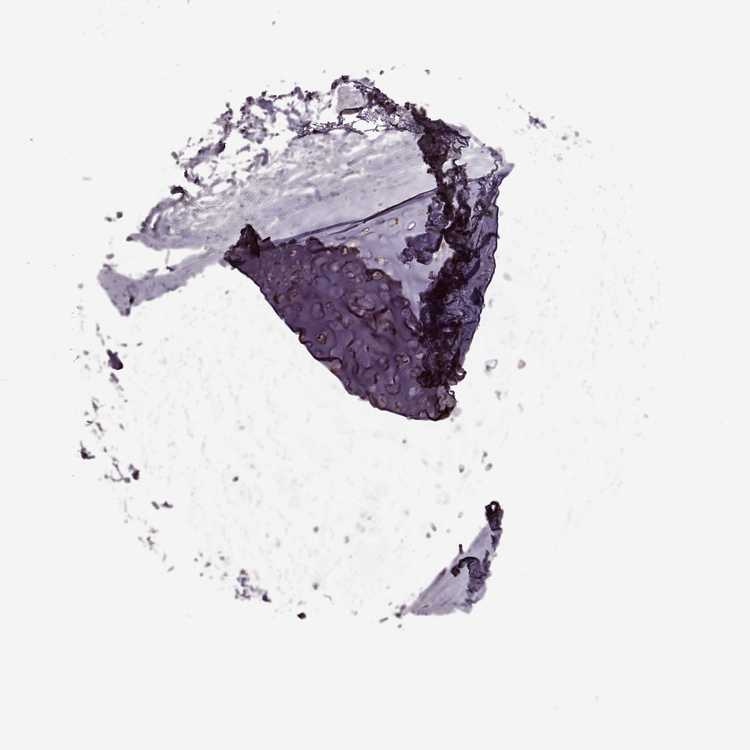

SOFT TISSUE 1 - Antibody stainingi

Antibody staining in the annotated cell types in the current human tissue is reported as not detected, low, medium, or high, based on conventional immunohistochemistry profiling in selected tissues. This score is based on the combination of the staining intensity and fraction of stained cells.

Each image is clickable and will lead to virtual microscopy that enables deeper exploration of all samples and also displays staining intensity scores, fraction scores and subcellular localization as well as patient and tissue information for each sample.

Antibody HPA034631Antibody HPA071347Antibody CAB033265Antibody CAB037325

Chondrocytes -Low--

Fibroblasts HighNot detectedNot detectedNot detected

Peripheral nerve Medium-MediumNot detected